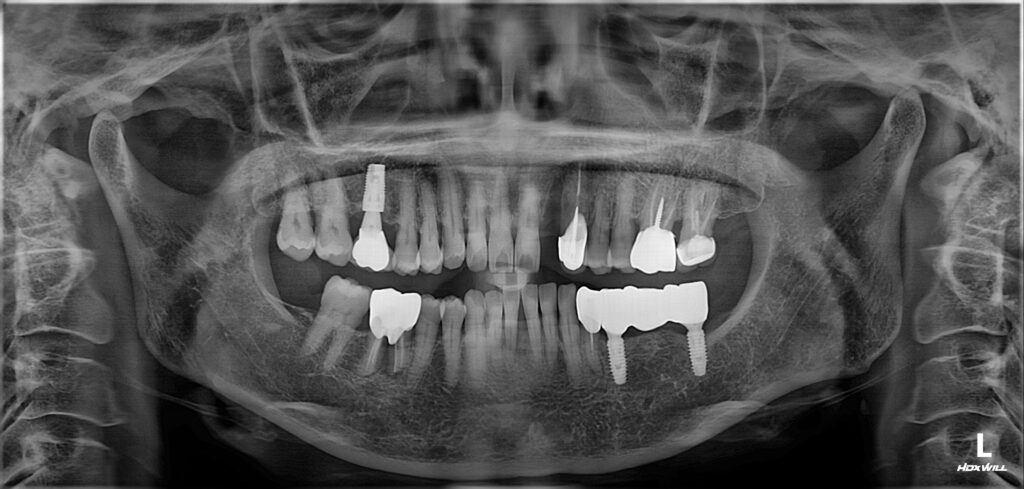

따라서 위쪽 앞니는 임플란트 식립과

아래쪽 앞니는 레진을 통해 틈을 메우는

치료를 진행하기로 하였습니다.

보험 임플란트 가능하셨고

콜라겐을 함유하고 있는 블럭형태의 골이식재를

사용하는 것이 움직임이 적기 때문에

더 예지성있는 형태를 만들수 있을 것으로 생각하여

진행하기 전 CT 촬영을 통해 정밀한 진단을 바탕으로

치료를 계획하였습니다.

뼈이식 후 임플란트 식립을 진행한 모습입니다.